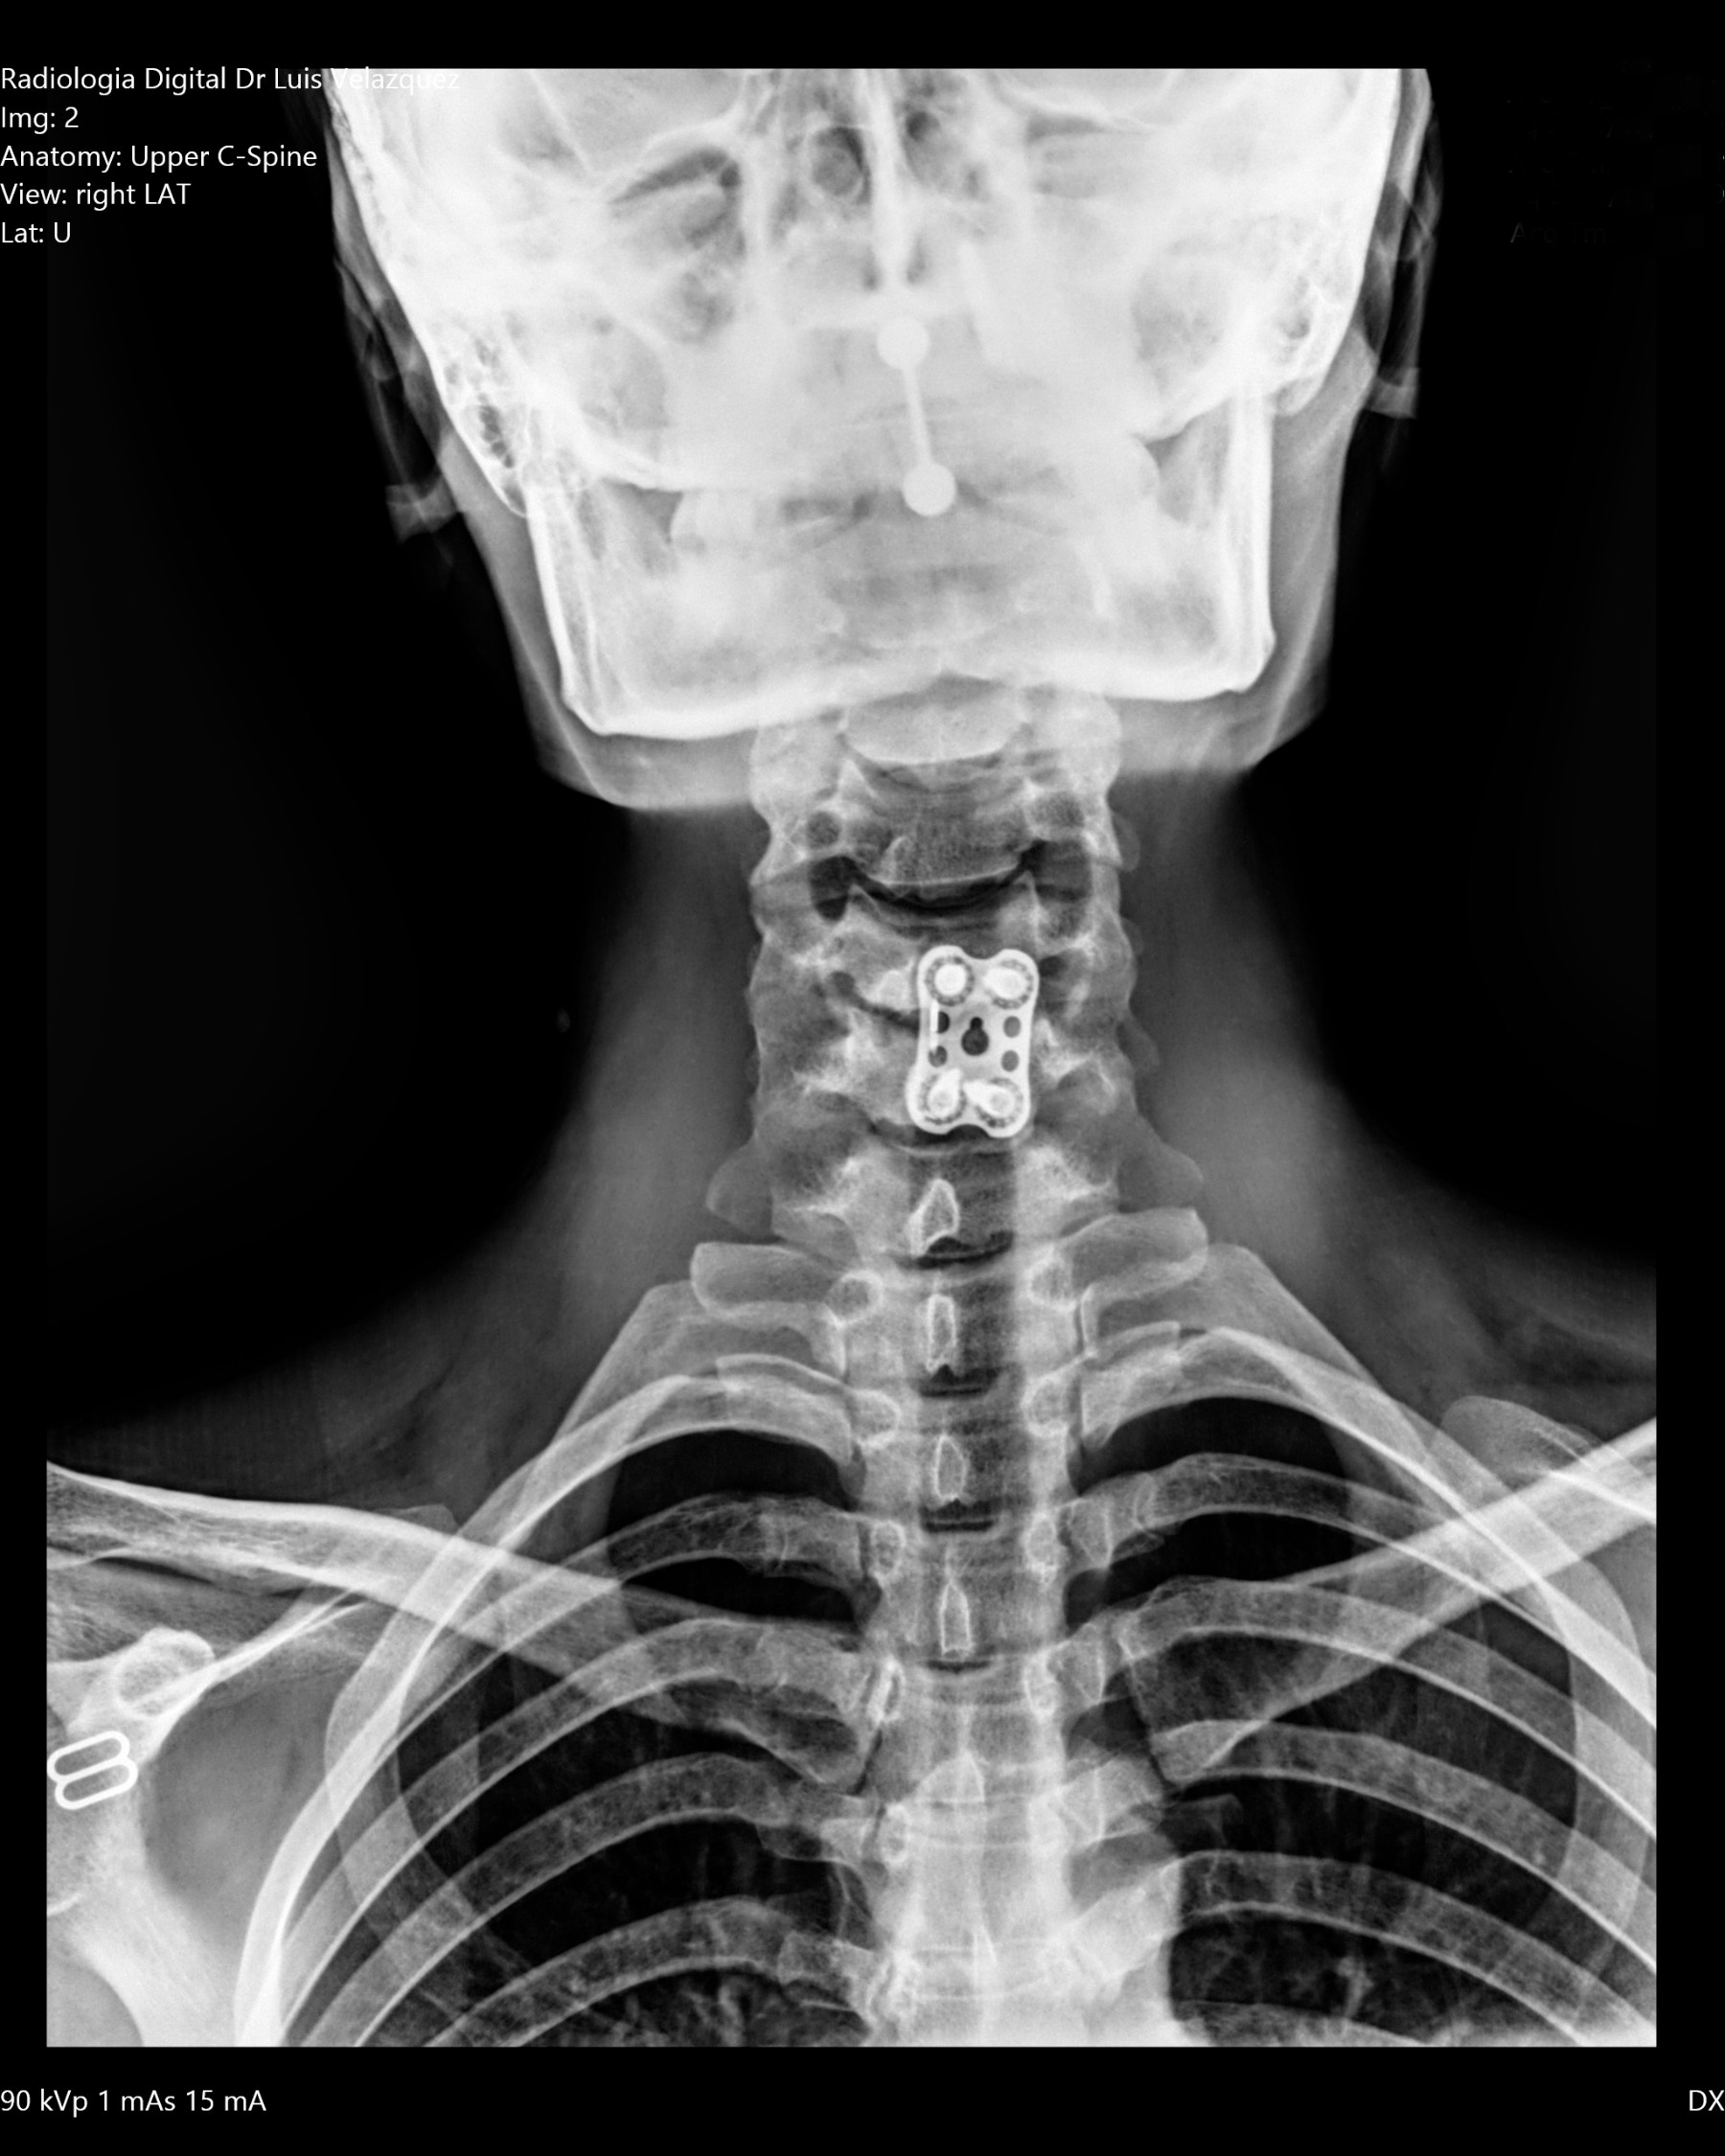

Radiología Digital como Herramienta Complementaria en el Dictamen de Bienes Muebles

Desde el descubrimiento de los rayos “X” y las placas radiográficas por Wilhelm Conrad Roentgen y su posterior difusión a través de la Asociación Físico médica de Wurzburg el 28 de diciembre de 1895, que fue la primera asociación que habló de los nuevos rayos que podían penetrar el cuerpo y fotografiar los huesos, ha habido muchos cambios tanto en la forma de obtener, procesar e incluso en la forma de visualizar, manejar y almacenar las placas radiográficas.